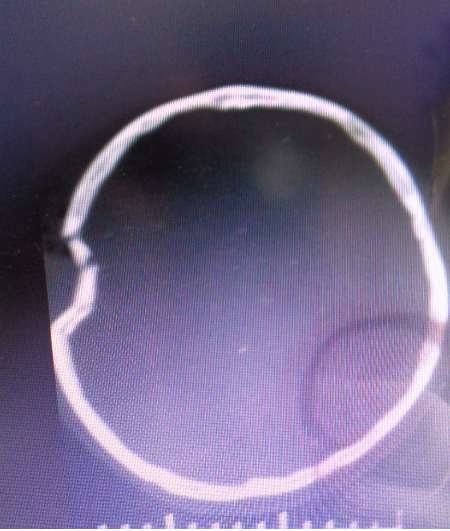

审阅某县医院2019年03月20日头颅CT片(片号XXXX),额顶部见颅骨凹陷性粉碎性骨折,周围头皮肿胀。颅内未见明显创伤性改变。

被鉴定人周某损伤部位及CT影像

????颅骨凹陷性粉碎性骨折